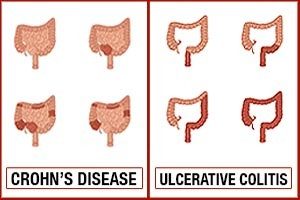

Crohn’s disease vs. ulcerative colitis, differences in symptoms, causes, and treatment

Crohn’s disease and ulcerative colitis are part of the group of conditions known as inflammatory bowel diseases (IBD). Prior to the 20th century, before the rise of hygiene and urbanization, inflammatory bowel disease was quite rare. Currently, IBD is found in developed countries and is believed to be caused by a lack of germ resistance development – although the exact cause is still unknown.

For those living with IBDs, their immune system mistakes food and bacteria in the gastrointestinal tract for an allergen or foreign substance, so it sends out cells to destroy it. The result of these attacks is chronic inflammation. Continue reading…